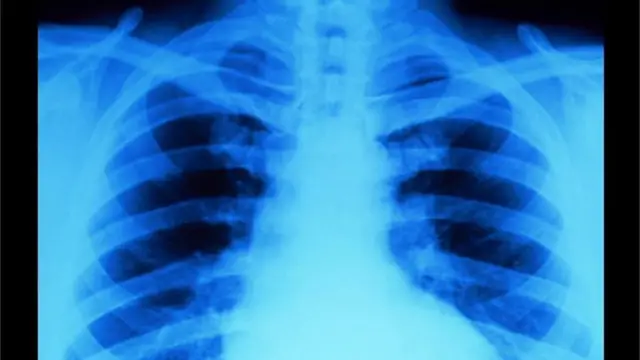

Después del nacimiento, se le puede hacer una radiografía al bebé para valorar en qué medida está extendido el daño en los huesos, pero la confirmación o clarificación del diagnóstico llegará con un análisis genético.